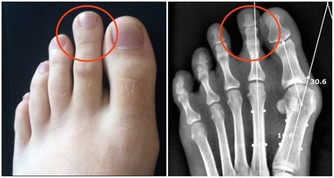

大魚大肉過後,是否有不斷放臭屁、便祕、肚子悶痛或大便變細等症狀?

如果一段時間後就恢復正常,就不必太擔心;

如果狀況持續1個月以上,可能是大腸病變的前兆,應小心為妙。

便祕、腹痛 大腸癌前兆

大腸癌的成因:「簡單說,是先有便祕,接著產生息肉,再病變成大腸癌。」大腸是由升結腸、橫結腸、降結腸及乙狀結腸等所構成,左側的大腸管徑比右 側大腸窄,當有腫瘤發生時,就會出現腸阻塞而引起便祕、腹脹甚至腹痛的情形。

因為糞便大多在左側的結腸成形,因此如果阻塞的狀況嚴重的話,所排出的糞便就 會有時還會參雜血絲, 嚴重到便祕及解血便情形。